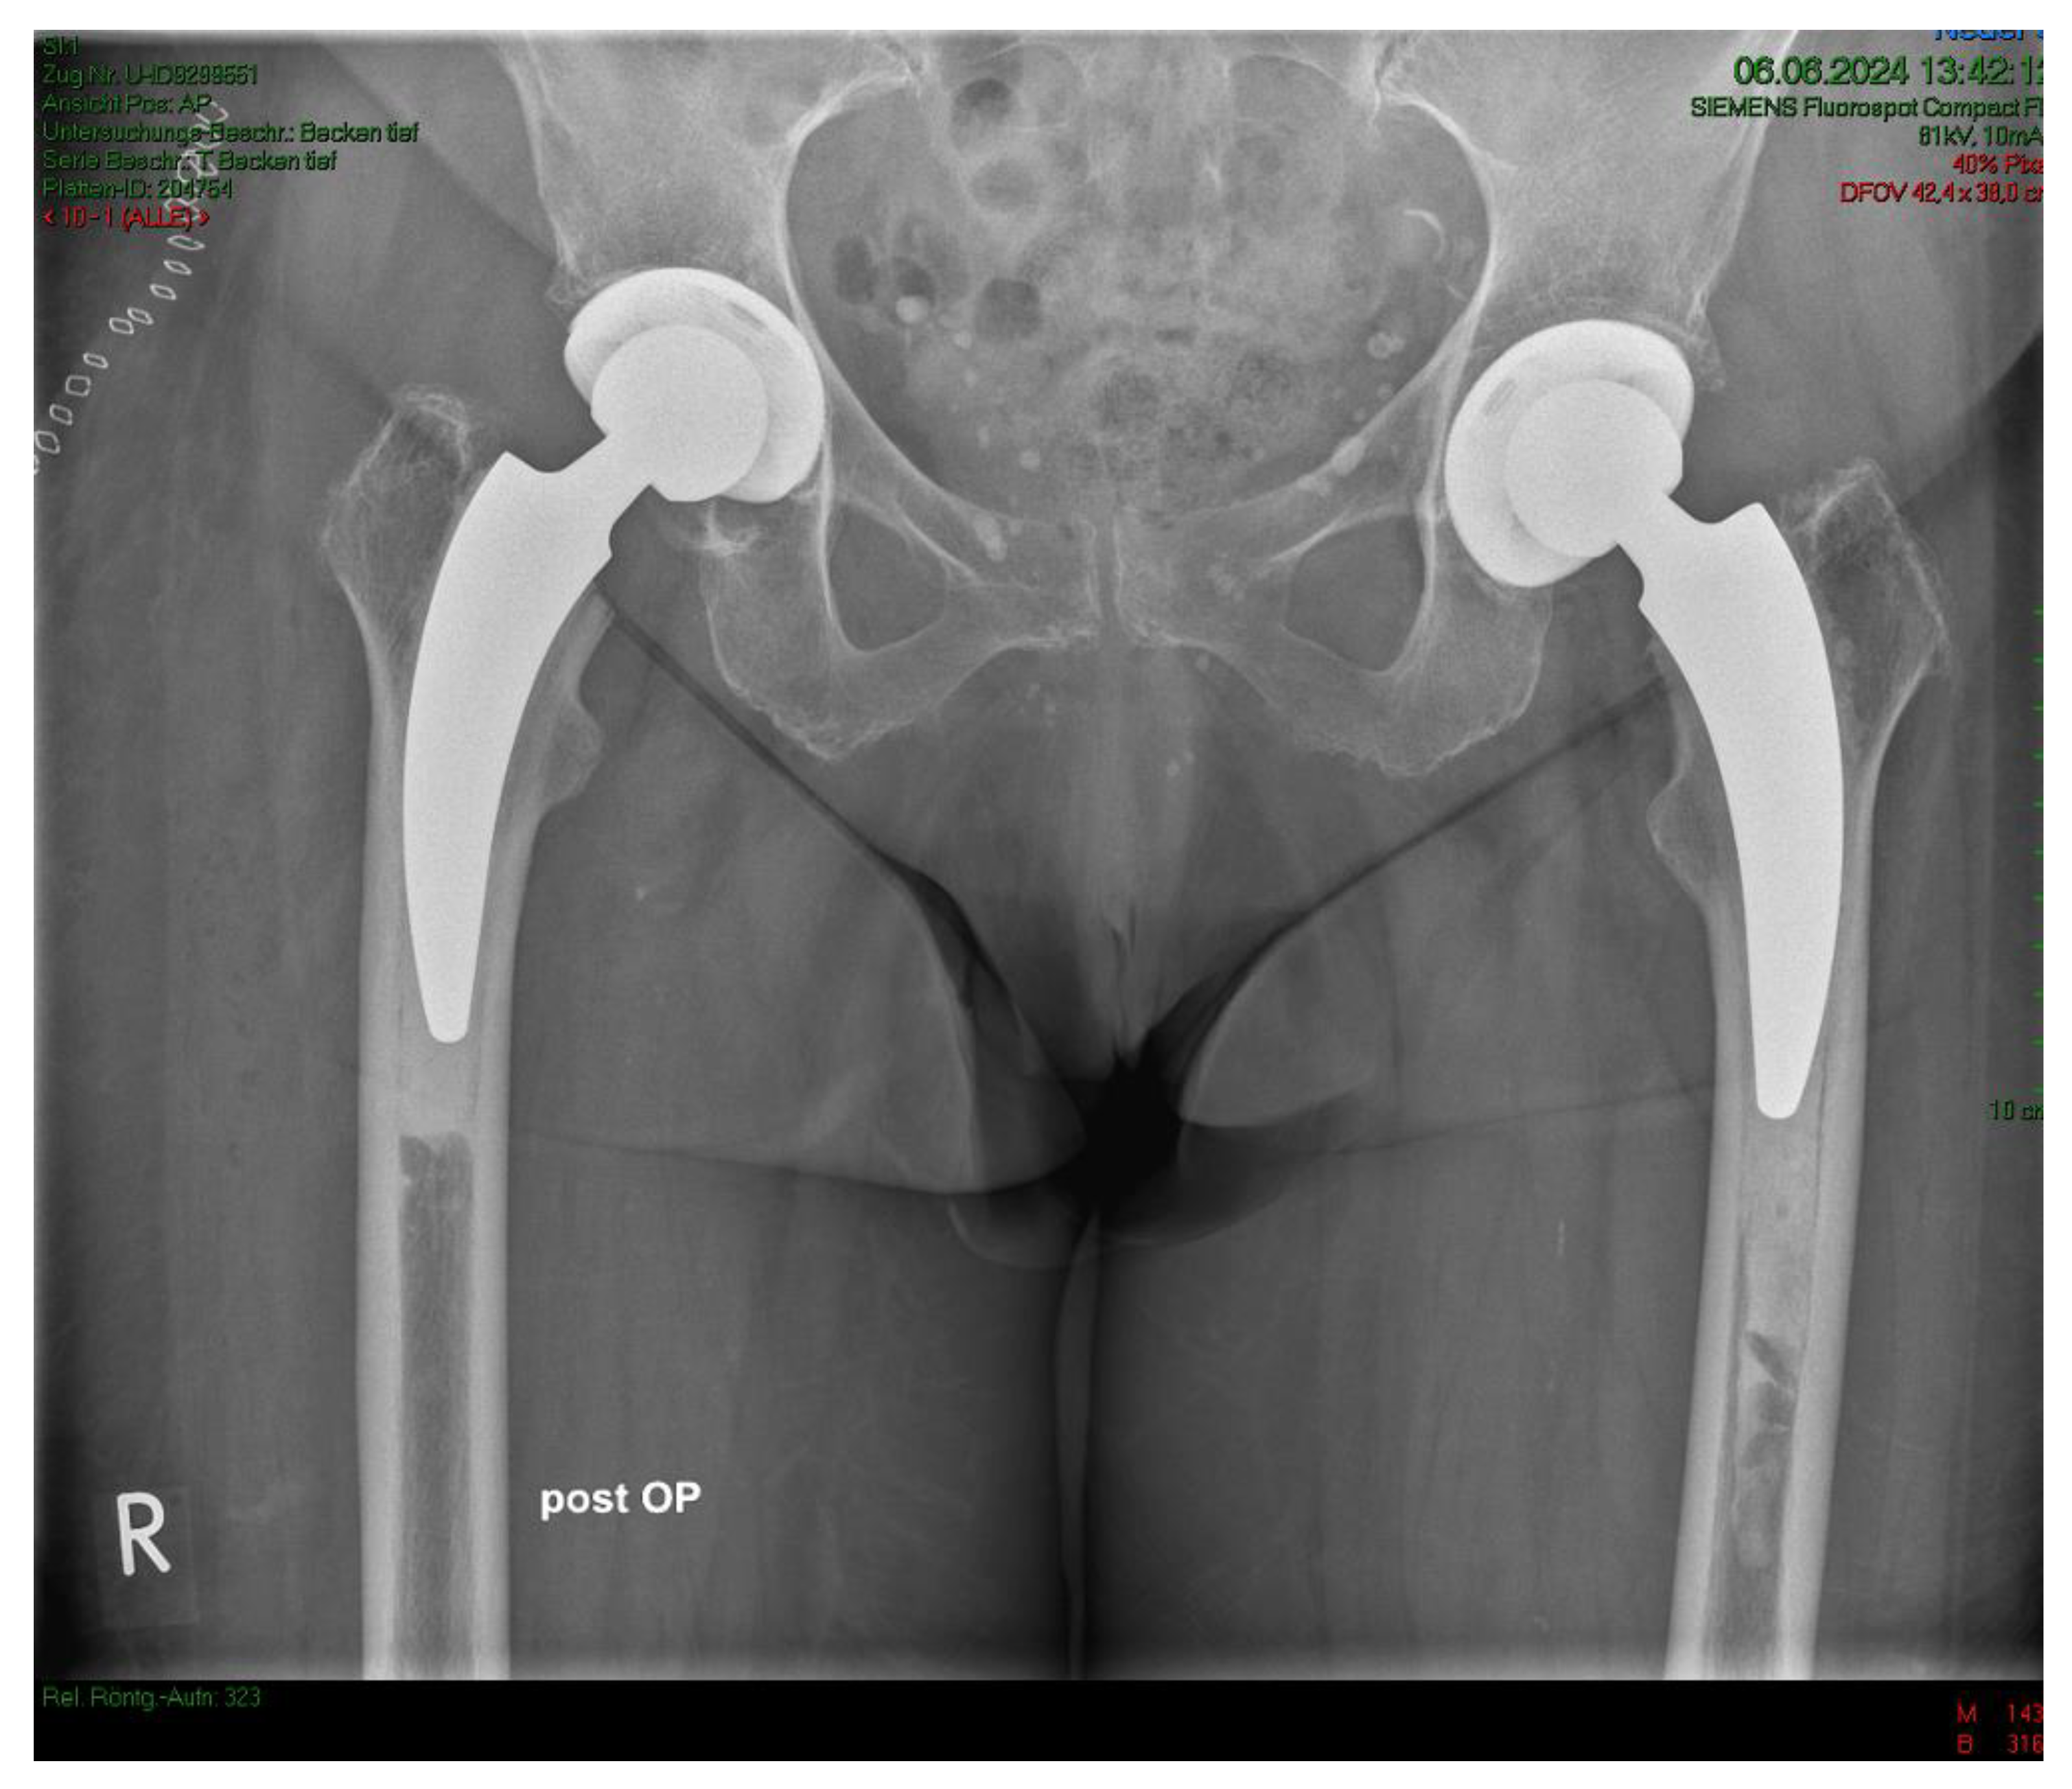

Of the 28 patients who underwent surgery, 5 withdrew their consent and 2 patients died due to unrelated causes. One prosthesis was explanted at 2 months postoperatively due to undersizing of the cement stopper, resulting in an inadequate cement mantle, which subsequently led to 14 mm of subsidence in the weeks following implantation. Hence, there were 20 patients with a 1-year follow-up. The mean HHS increased from 49.4 ± 13.9 preoperatively to 93.6 ± 6.9 at the final follow-up. No pain was reported by 19 patients at the final follow-up, with only occasional slight pain in one patient. The mean UCLA score increased from 3.5 ± 1.5 preoperatively to 5.1 ± 1.9 at the one-year follow-up. The mean HOOS-PS score increased from 44.2 ± 22.1 preoperatively to 60.0 ± 28.6 at the one-year follow-up. The FJS score was 68.3 ± 14.6 at the one-year follow-up. One patient experienced leg shortening of 10 mm. Periarticular ossification Brooker 1 was identified in three patients. One patient experienced axial subsidence of 2 mm. There were no postoperative infections. No radiolucent lines were observed, and none of the patients presented with osteolysis. A representative case is presented. Preoperative planning facilitated the achievement of anatomic restoration, as depicted in Figure Figure 3 demonstrates the correct postoperative positioning of the femoral stem and a complete cement mantle.

Figure 3. a Case #2 Osteoarthritis, female, 85 years old, bilateral sequential implantation of an A2 stem, Dorr B-C femora.

Preprints 111236 g003a